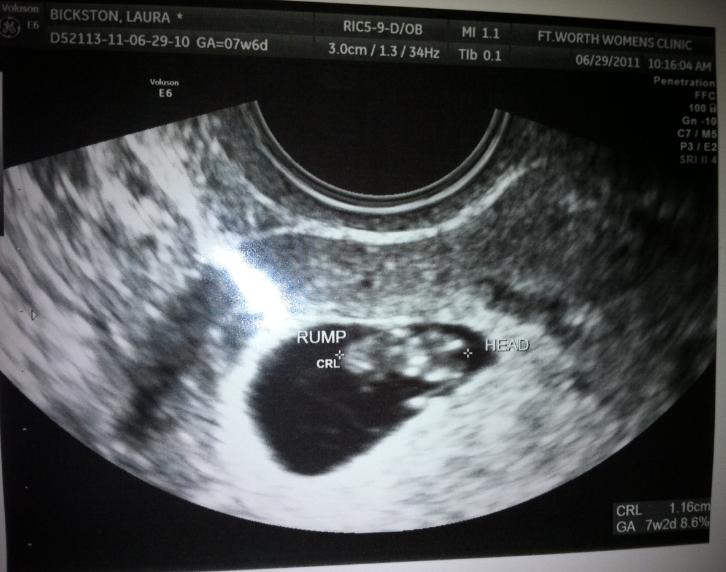

Here is Baby Bickston's sonogram from today!

He believed after that! :) We were in shock for a couple of days. It's like, you go so long wondering if you really can get pregnant and then one day..you are! It has been pretty hard keeping it a secret, more so for Matt than me. Mainly because he has to go to work everyday and not say anything! Poor thing, was so excited he wanted to tell EVERYONE!So- fast forward to today. We got to see our precious little baby! I am measuring at 7 weeks and 2 days. To me, it looks like a little peanut! The most wonderful sound in the entire world was his/her heartbeat. It was 144 bpm. I cannot wait for what the rest of the pregnancy holds!